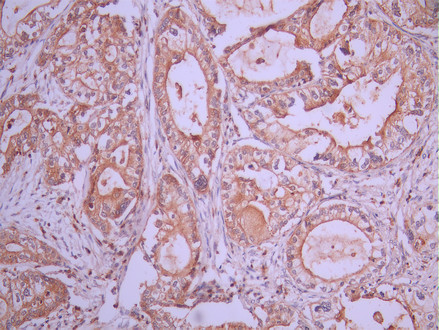

IHC image of CSB-RA632615A0HU diluted at 1:100 and staining in paraffin-embedded human pancreatic cancer performed on a Leica BondTM system. After dewaxing and hydration, antigen retrieval was mediated by high pressure in a citrate buffer (pH 6.0). Section was blocked with 10% normal goat serum 30min at RT. Then primary antibody (1% BSA) was incubated at 4°C overnight. The primary is detected by a Goat anti-rabbit polymer IgG labeled by HRP and visualized using 0.05% DAB.